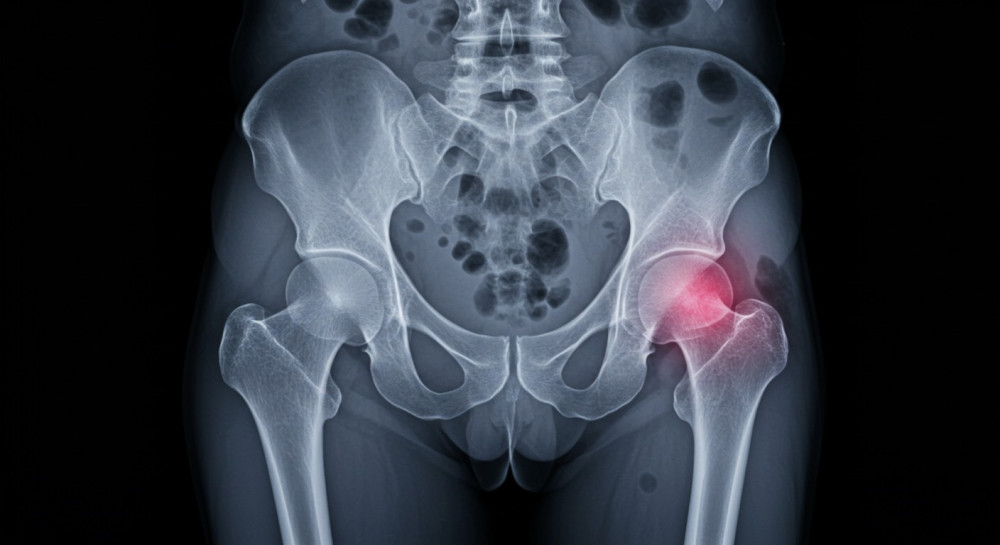

更年期と股関節の深い関係

女性ホルモン「エストロゲン」には、関節や靭帯を柔らかく保つ働きがあります。

ところが更年期を迎えると、このエストロゲンが急激に減少。

結果として関節のクッション性が低下し、股関節にかかる負担が一気に増えるのです。

特に女性は骨盤が広く、股関節の受け皿が浅いため、構造的にも負担がかかりやすい。